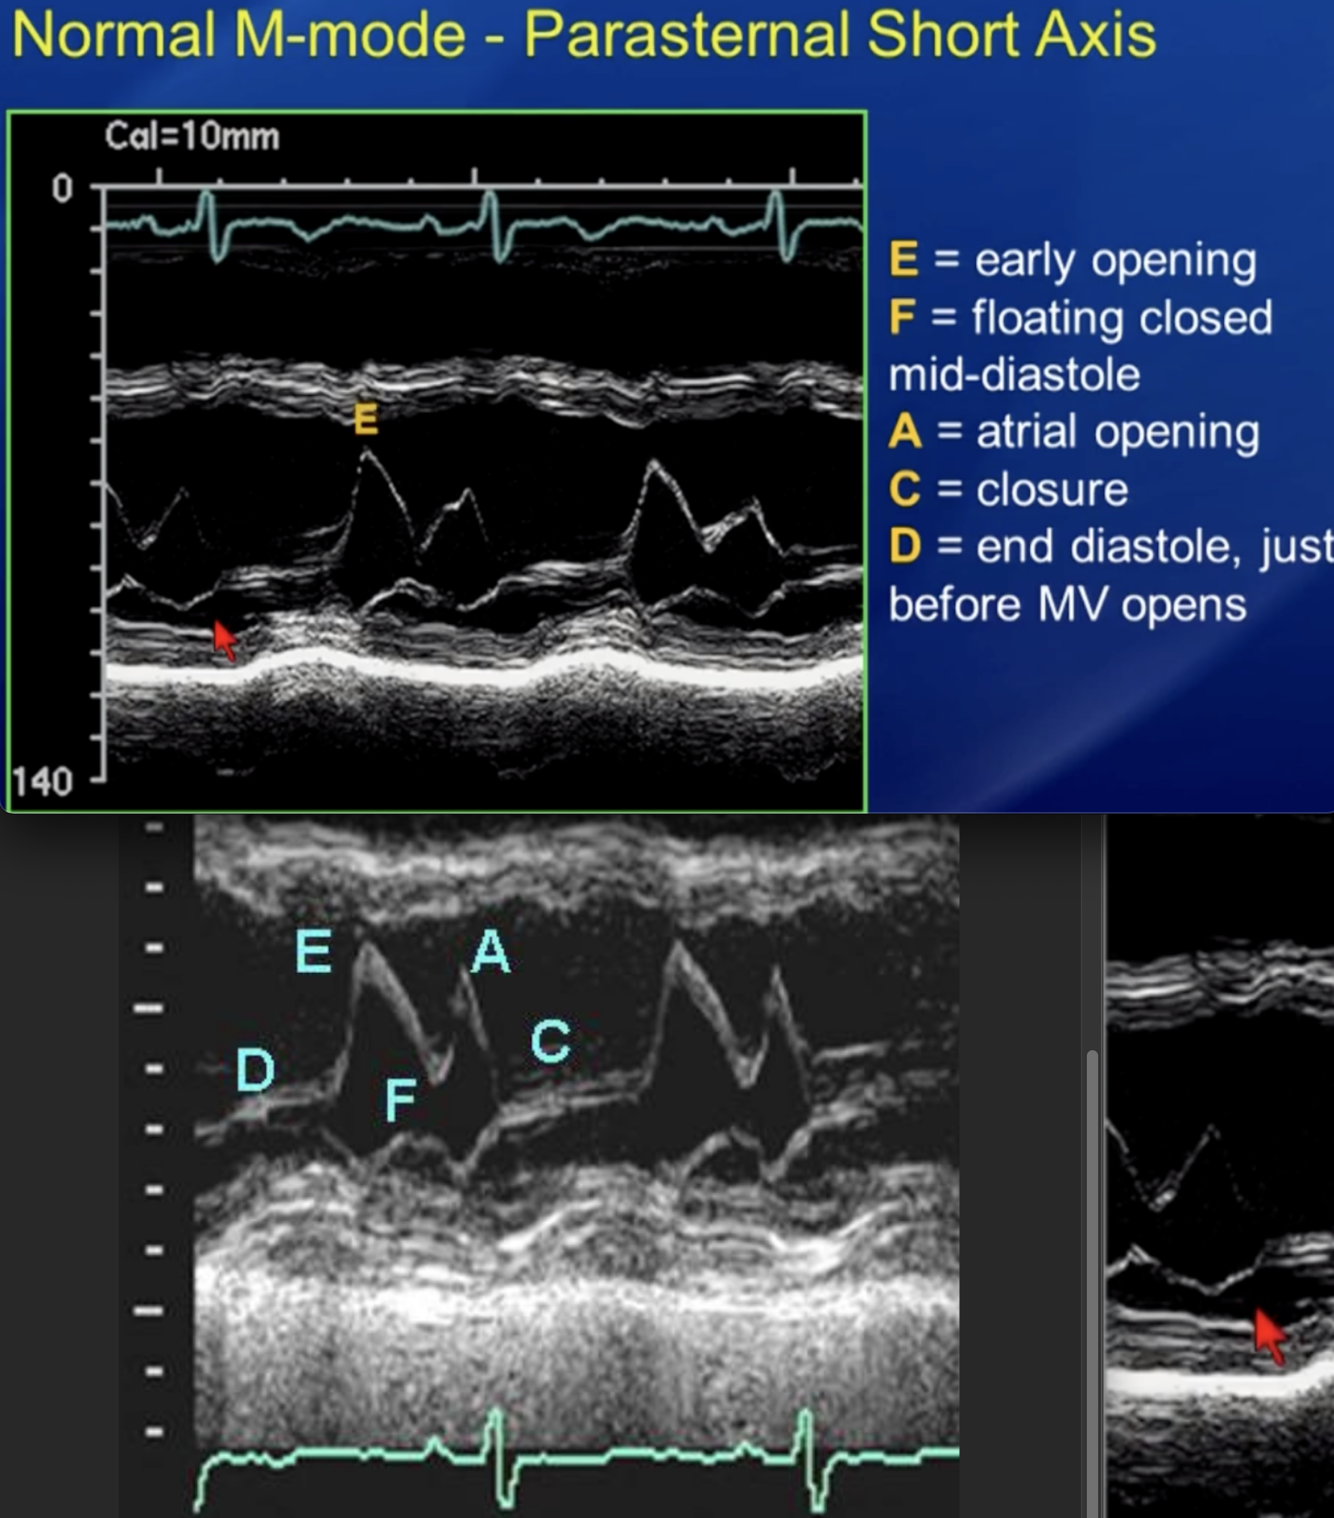

Describe the findings of M mode: